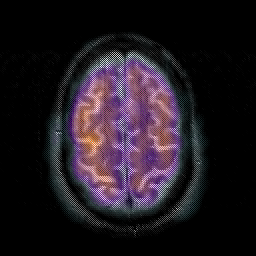

Subacute Stroke overlay -- Slice #19

[Home][Help][Clinical] Slice 19